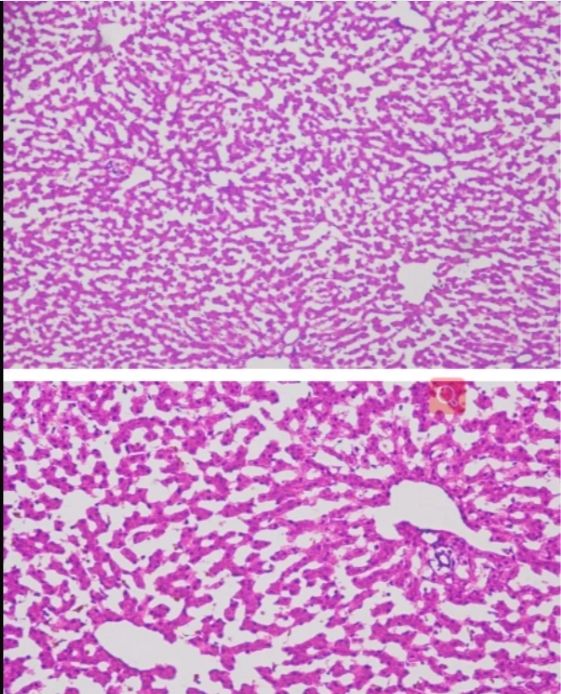

冰凍切片

此外,在染色性能方面,兩種切片技術也各有千秋。石蠟切片適用于多種染色技術,如H&E染色等,能夠清晰地展示組織的細胞結構和形態。而冰凍切片則更多地應用于免疫組化和原位雜交等特殊染色技術,為科研人員提供了更多維度的觀察手段。